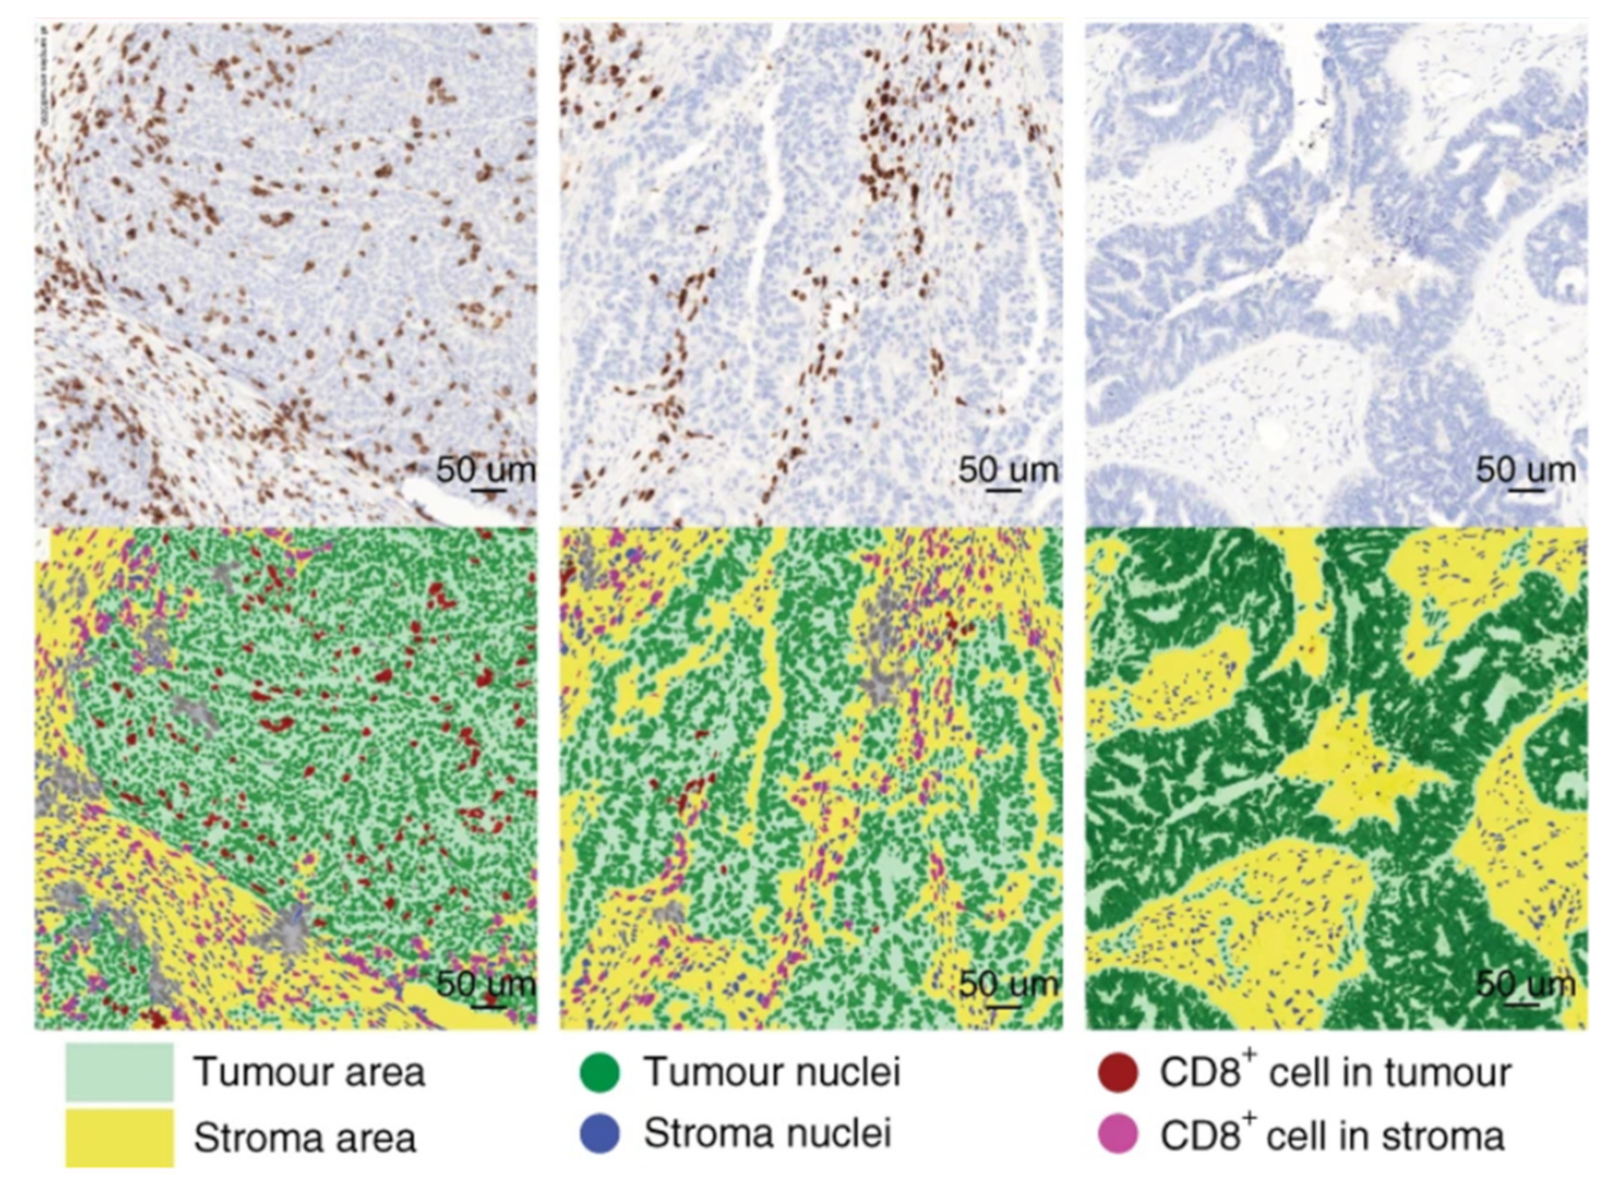

Applications of AI in Cell Segmentation

Accurate cell segmentation is the foundation of tissue cytometry. AI-powered methods, such as deep learning, improve accuracy, reduce errors, and streamline workflows. TissueGnostics integrates AI-based segmentation with phenotyping, spatial analysis, and dot detection.

What is Spatial Phenotyping?

Spatial phenotyping combines whole-slide imaging and advanced analysis to study cellular phenotypes in their native context. This approach is key in immunotherapy research, enabling insights into the tumor microenvironment and supporting informed treatment strategies.